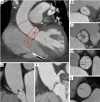

Figure 4

Cardiac CT with iterative reconstructions. (A) Volume rendering; (B) coronary artery tree map; (C,D) multiplanar reconstructions of the coronary arteries.